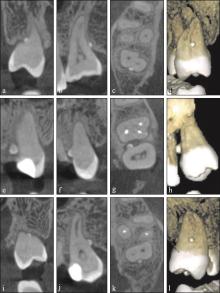

Fig 1

CBCT images of multiple enamel pearls in bilateral maxillary second molars of the same patient"